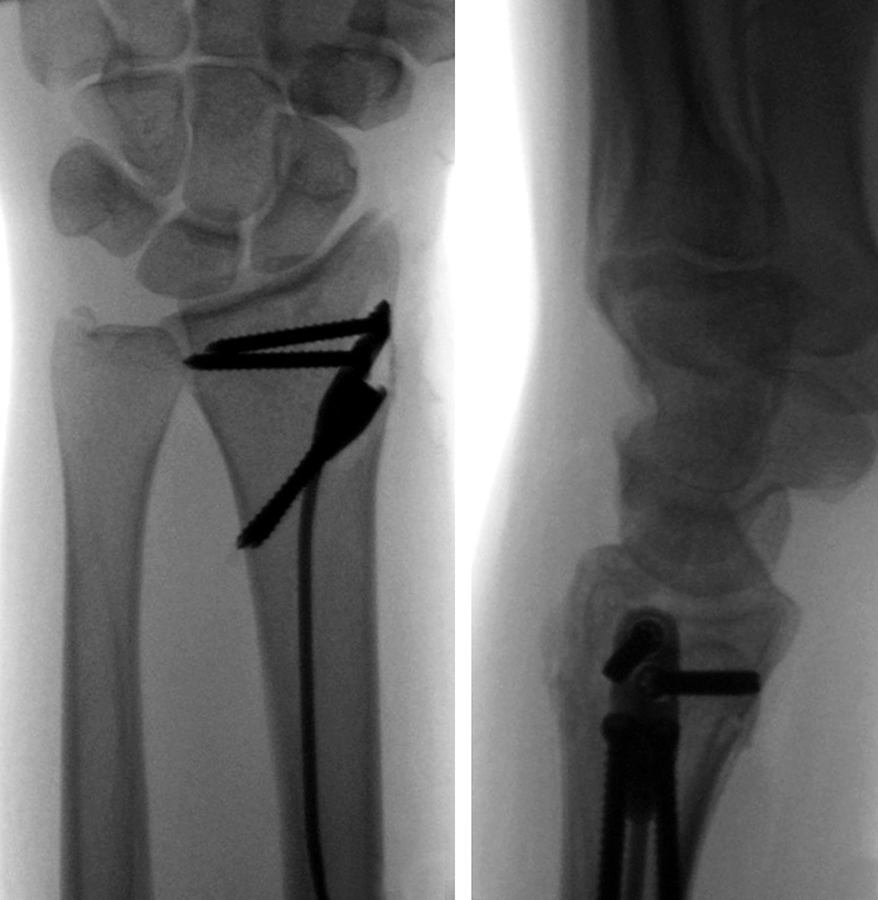

The patient was a 25-year-old woman who sustained a displaced, unstable extraarticular fracture of the left distal radius while snowboarding.

After closed reduction a dorsal re-dislocation of 25° occurred (Fig 3a). There are additional apparent signs of instability: dorsal comminution (Fig 3a) and fracture of the ulnar styloid (Fig 3b). Therefore, a considerable potential for further dislocation is present which is likely to occur in a cast. This young, active, and demanding patient wishes to return to her activities as early as possible. This can only be achieved with an operative fracture fixation. The nail was chosen instead of a plate. This allowed an almost instant functional use of her hand, which allowed her to return to work at 2 weeks postoperatively without additional fixation or a splint and full unprotected function of her wrist at 6 weeks.